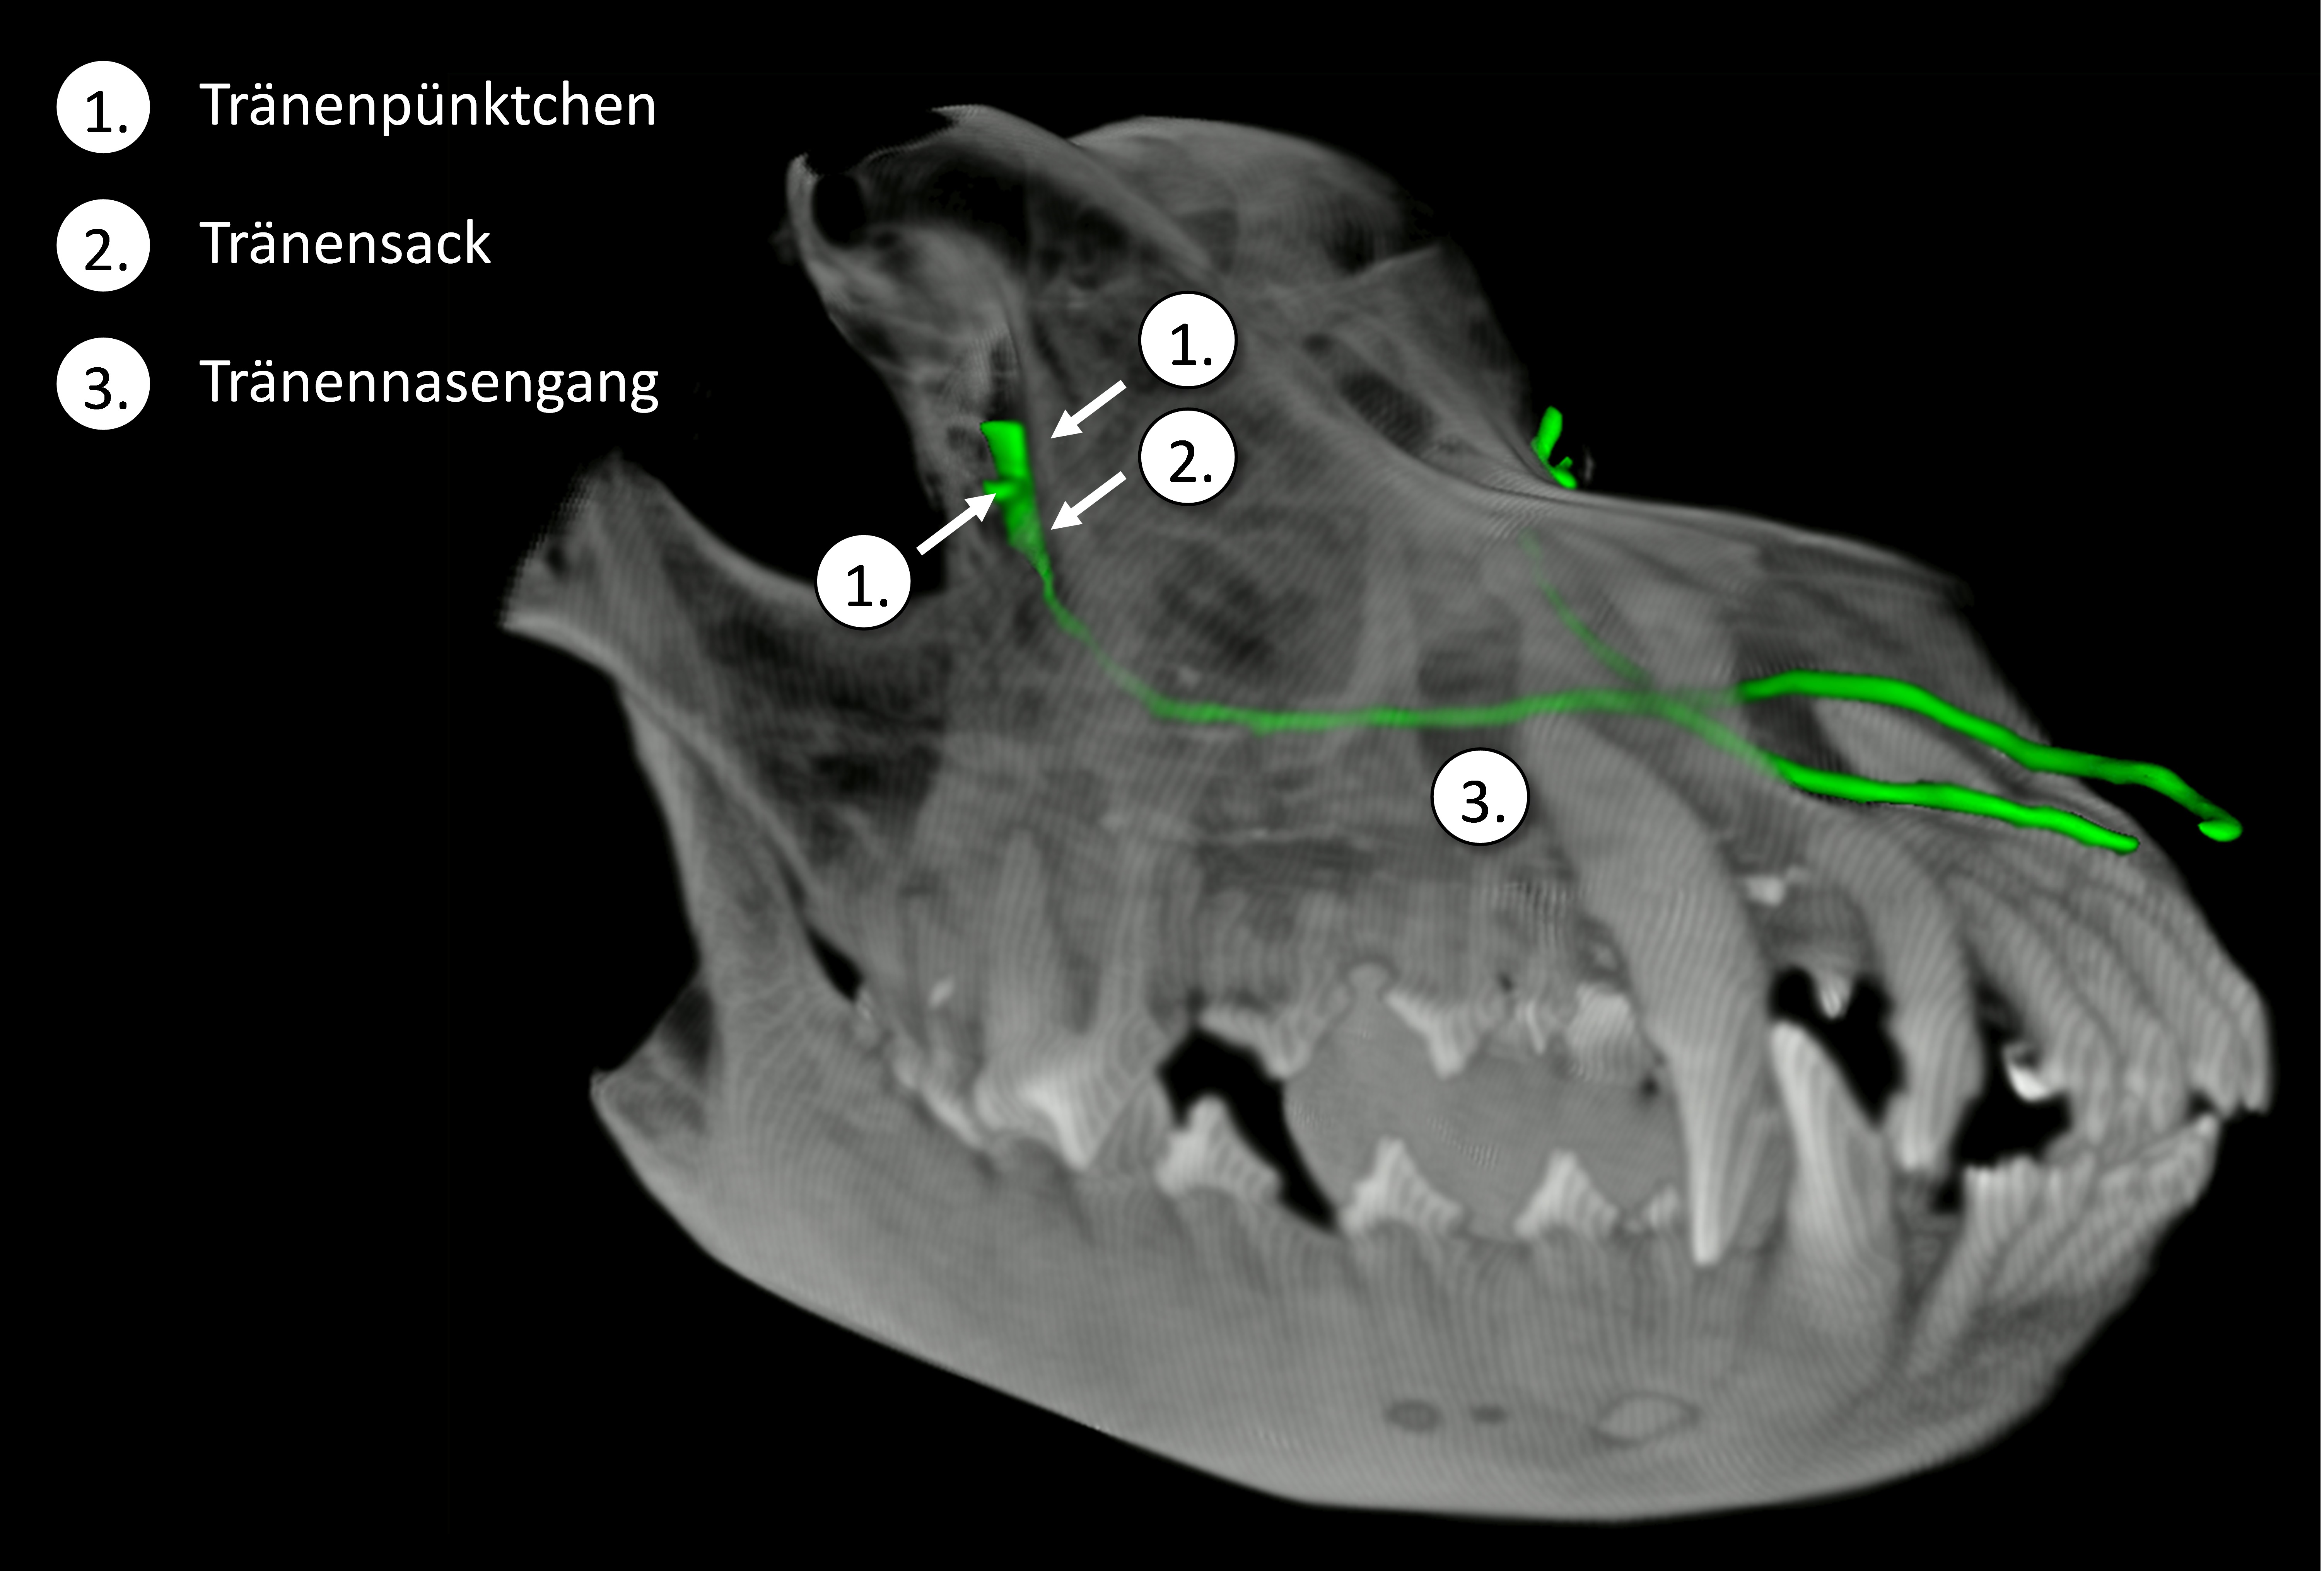

Tränenwege im Schädel dargestellt

Veröffentlicht am 21. Februar 201721. Februar 2017Originalgröße 6009 × 4071